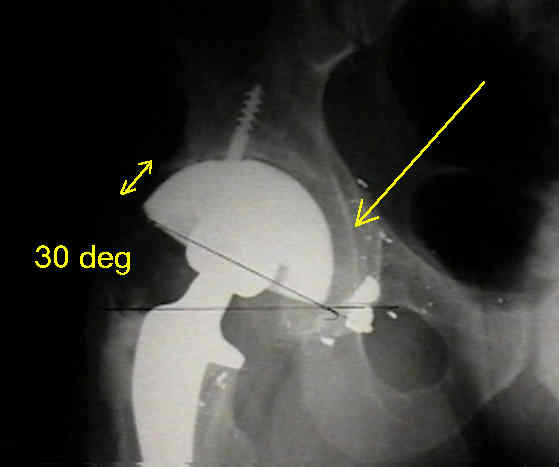

Case Example

- 35-year-old male w/ near anklyosed hip following a GSW to the hip;

- preoperative films appeared to indicate that little or no medialization was necessary;

- postoperative films, however, indicate that the cup was lateralized (hence, reaming was inadequate);

- in retrospect, the radiographs which are rotated externally (like an iliac oblique) tend to falsely minimize the necessary amount of medialization where as X-rays which are rotated internally (like an obturator oblique), tend to over-estimate the necessary amount of medialization